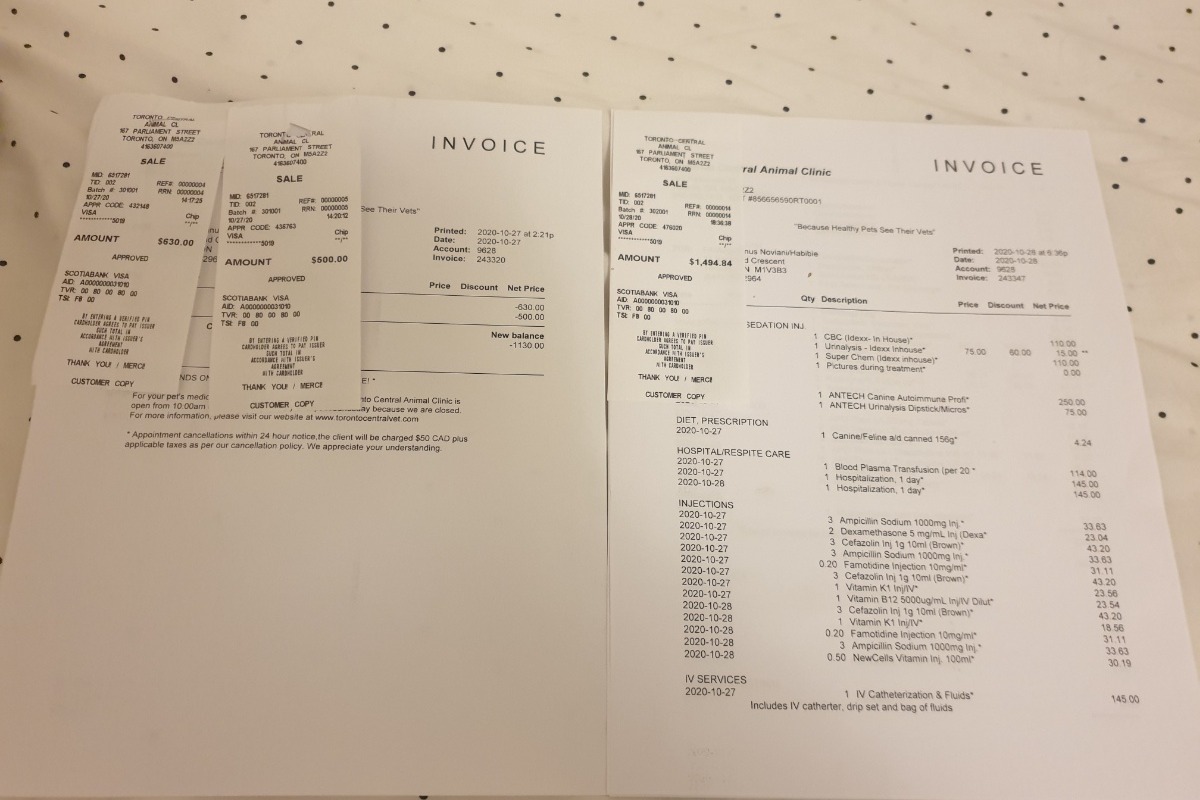

Gooey, Male.Gooey has been my best friend for 4 years, I got him since he was still a 3.5mths puppy, I brought him with me on the plane from Indonesia. While it is also the first time with me arriving in Canada. We going through a lot of difficulties together, while this pandemic also make everything more difficult for us. Right now his vet bills totalled $3401.

I have peoples donated to me directly totalled $1120. So I just need a little bit more kindness from all of you, please.